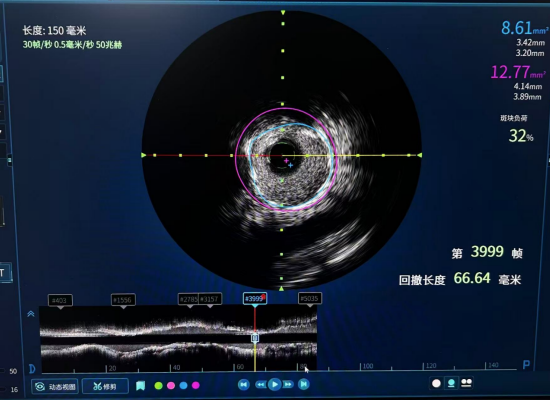

(IVUS术前)

(IVUS术后)

面对这一挑战,医院心血管专家团队决定启用血管内超声(IVUS)技术作为本次手术的“导航核心”。IVUS堪称介入医生的“第三只眼睛”,它能将一枚微型超声探头通过导管直接送入血管内部,从管腔内进行360度全方位扫描,生成高清的血管横断面图像。

“如果说造影是看一条隧道的平面轮廓,那么IVUS就是派出了一个探测机器人,进入隧道内部,将隧道的壁厚、内部堵塞物的成分、大小,乃至哪里的墙壁需要加固,都看得一清二楚。”成都市第三人民医院派驻心内科专家刘火军主任解释道。